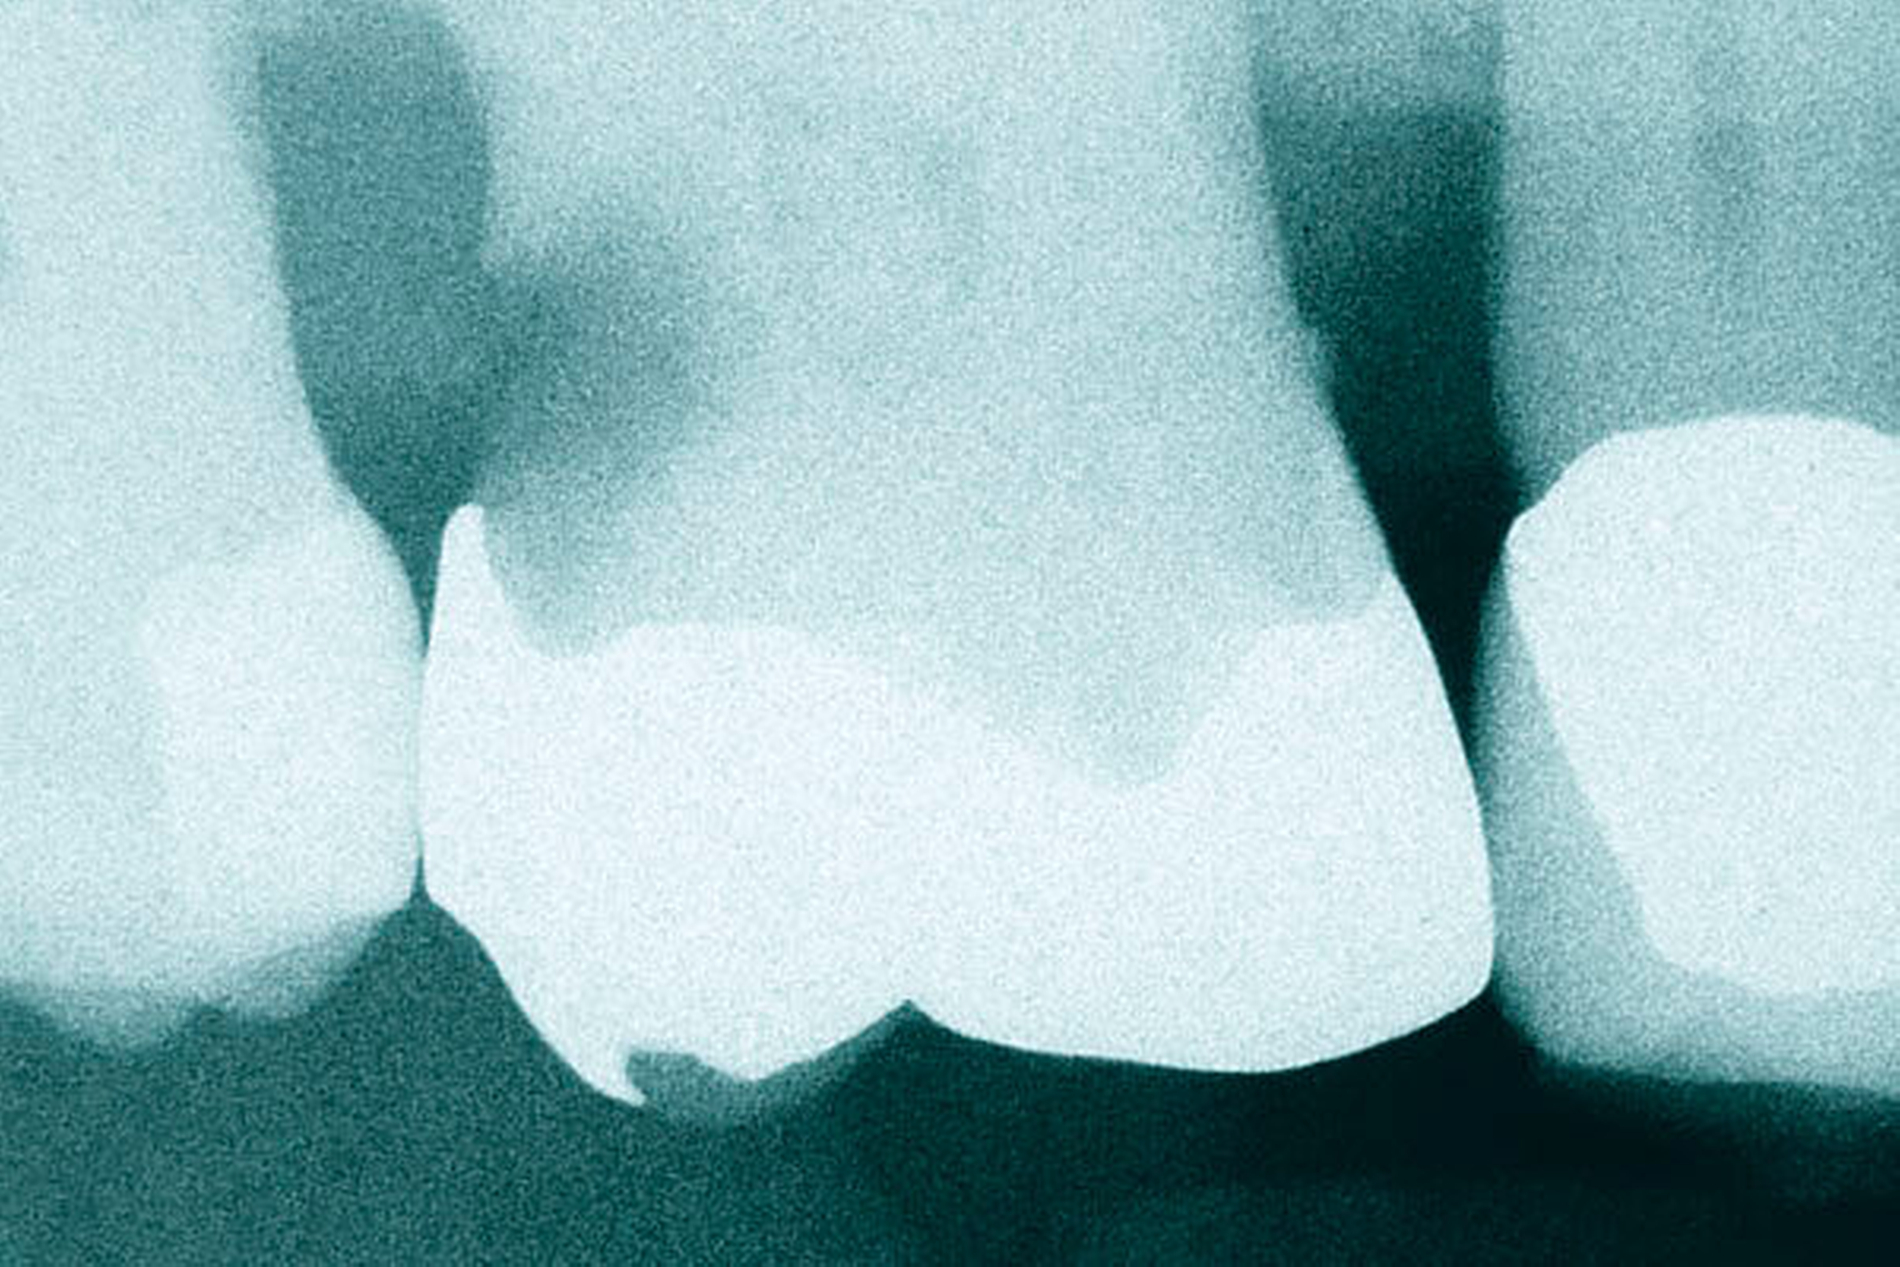

In den Abbildungen 1 bis 3 werden Optionen für frugale Interventionen auf restaurativem Sektor aufgeführt. Es handelt sich um direkte Vollüberkronungen im Frontzahnbereich (hier: hergestellt in R1-Technik / einphasig) (Abbildung 1), direkte Teilüberkronungen im Seitenzahnbereich (hier: hergestellt in R1-Technik / einphasig) (Abbildung 2), Reparatur-Restaurationen im Seitenzahnbereich (hier: hergestellt in R2-Technik / zweiphasig) (Abbildung 3). Technische Einzelheiten zur Vorgehensweise und den Ergebnissen sind an anderer Stelle beschrieben (Literatur siehe oben).

Am Beispiel von Abbildung 1 (stark zerstörte Zahnkrone eines Schneidezahns) kann das Prinzip der frugalen Intervention erläutert werden:

Früher wurde für die hier beschriebene Ausgangssituation folgendes Procedere gewählt:

Wurzelkanalbehandlung des vitalen Zahns als Voraussetzung für eine Stiftversorgung

Einsetzen eines Wurzelkanalstifts

Einsetzen einer indirekt gefertigten Stiftkrone

Durch die Erfolge der Adhäsiv- und Komposittechnik kann heute folgendermaßen vorgegangen werden:

Verzicht auf Wurzelkanalbehandlung / Erhaltung der Vitalität des Zahns

Verzicht auf Wurzelkanalstift

direkte minimalinvasive Kompositkrone (Verzicht auf indirekte Vorgehensweise)

Die potenziellen medizinischen und ökonomischen Vorteile dieser frugalen Intervention sind vielfältig:

Schonend: Die oralen Strukturen werden geschont und die Versorgung ist hinreichend stabil. Durch den Verzicht auf Wurzelkanalstifte wird das Wurzelfrakturrisiko reduziert. Zudem können Material-, Geräte- und Personalressourcen aus Praxis und Techniklabor, die beim klassischen Vorgehen anfielen, reduziert werden.

Bezahlbar: Hier ist anzumerken, dass die Kosten unter anderem von der zahnärztlichen Expertise abhängig sind: Zahnärzte, die mit direkten Restaurationen große Erfahrung haben, können zügiger und mit besserem Erfolg arbeiten als Kollegen mit geringerer Erfahrung auf diesem Gebiet; die Behandlung ist gleichwohl anspruchsvoll und deshalb nicht „billig“. Eine direkte Vorgehensweise kann, muss aber nicht automatisch zeit- und kostensparender sein als eine Versorgung mit indirekt hergestellten Werkstücken.

Gut genug: Ästhetische Feinheiten lassen sich bei direkten Restaurationen nicht immer in gleicher Perfektion einarbeiten wie bei indirekt gefertigten Kronen, auch die Stabilität des Hochglanzes lässt bei einigen Kompositpräparaten noch zu wünschen übrig. Andererseits erlauben die direkten Verfahren inzwischen mitunter sehr flexible Vorgehensweisen, die sich auch mit Farb- und Formkorrekturen von Zähnen kombinieren lassen. Die Erwartungen eines großen Teils der Patienten werden hinreichend erfüllt und die Nutzen-Risiko-Relationen wie auch die Aufwand-Kosten-Relationen erscheinen – wenn auch nicht durchgängig – so doch zumindest in vielen Fällen günstig.